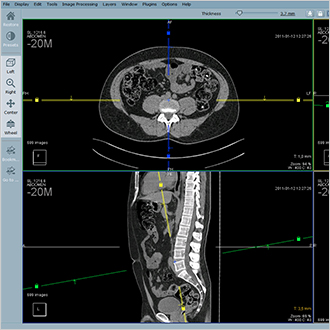

TM-PACS

Permet de compresser, de sécuriser, de stocker et de visualiser des images radiographiques à l'aide d'outils d'affichage et de visualisation de pointe (zoom, loupe, annotations, mesure de distances, suivi des mesures, etc.). L'utilisateur peut visualiser simultanément des images coronarographiques, PET et de médecine nucléaire, ainsi que des images d'imagerie plus classiques (IRM, scanner, échographie, etc.). L'utilisation d'étiquettes associées aux examens vous permet de créer des groupes d'examens et d'y accéder en un seul clic. Un système de recherche personnalisé vous permet d'accéder très rapidement au dossier du patient ou à l'examen souhaité. L'affichage est optimisé pour permettre un affichage multi-écrans, ainsi que l'intégration des logiciels RIS et PACS installés sur les mêmes postes de diagnostic.